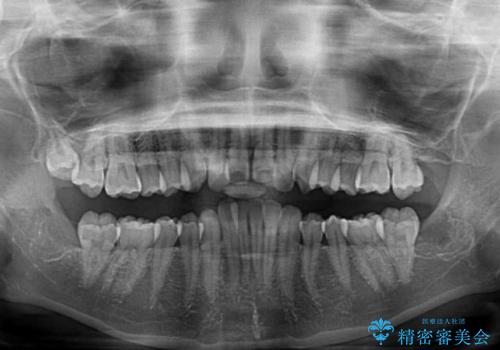

左右ともに上顎奥歯が外を向き、下顎奥歯が内側に倒れているシザーズバイトであったため、補助装置により改善することとしました。

上下の咬み合わせは、下顎に対して上顎が相対的に前方にあったため、奥歯のシザーズバイト改善後に上顎左右第一小臼歯2本を抜歯し、上顎前突を改善していくこととしました。

左側の咬み合わせと上下正中の位置をコントロールするために時間がかかりましたが、事前に思い描いた通りの歯列に整い、患者様には大変満足していただきました。